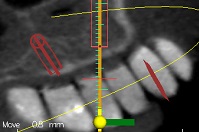

עקב חוסר בעצם ואי רצון מצד המטופל לעבור הרמות סינוס בוצע תיכנון ממוחשב של מיקום השתלים עוד בטרם ההשתלה.

ההשתלות בוצעו דרך שבלונה שהוכנה במדפסת תלת מימד בהתאם לקובץ הממוחשב.